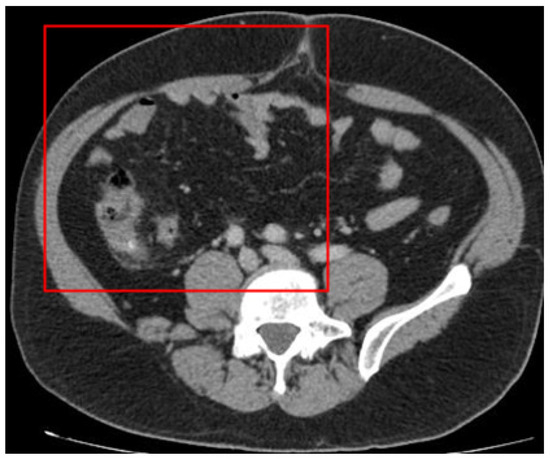

We focused on the region where the appendix is typically situated, which is the right side of the body (left in the figure). Raw images were partitioned into four sections according to the Cartesian plane system. The appendix in the dataset images is situated in the upper-left section and measures 250 × 600 pixels. Appendicitis was excluded from other regions where the appendix could not be located. The image size was therefore reduced from 1255 × 515 pixels to 250 × 600 pixels for analysis (Figure 4).

Figure 4. The image section used for deep learning (the red square).